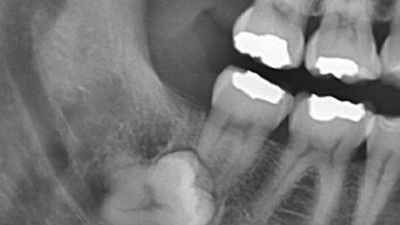

이 정도면 사랑니 발치 고난도라고 합니다. 문외한인 제가 봐도 왠지 움찔하게 되네요...;;